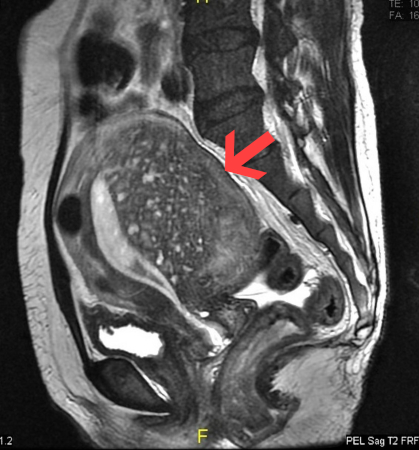

- MRI